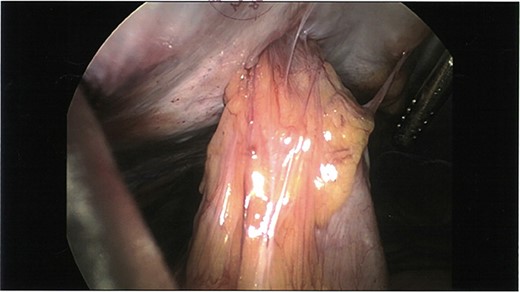

We deduce that during the primary LABG insertion procedure, a loop of small bowel and its accompanying mesentery was unknowingly caught in the expandable prongs of the laparoscopic RapidPort (Fig. 3) and hitched to the anterior abdominal wall. On the removal of this port, it appears that the segment of small bowel remained tethered with perforation contained within the abdominal wall.